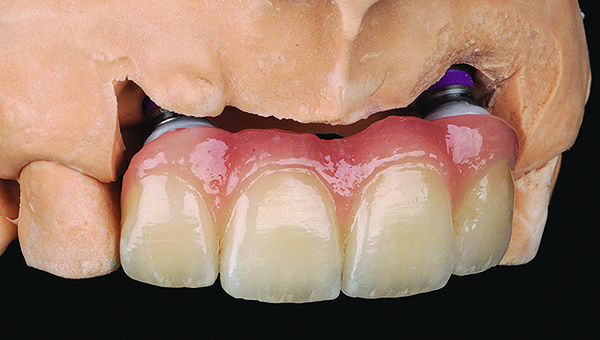

Fig 13. Porcelain-layered zirconia framework (CL-IIIb) with layered pink porcelain for the gingiva (Fig 13); final image in the mouth of the porcelain-layered zirconia framework (Fig 14) (images courtesy of Aram Torosian, MDC).

Figure 13

Fig 14. Porcelain-layered zirconia framework (CL-IIIb) with layered pink porcelain for the gingiva (Fig 13); final image in the mouth of the porcelain-layered zirconia framework (Fig 14) (images courtesy of Aram Torosian, MDC).

Figure 14